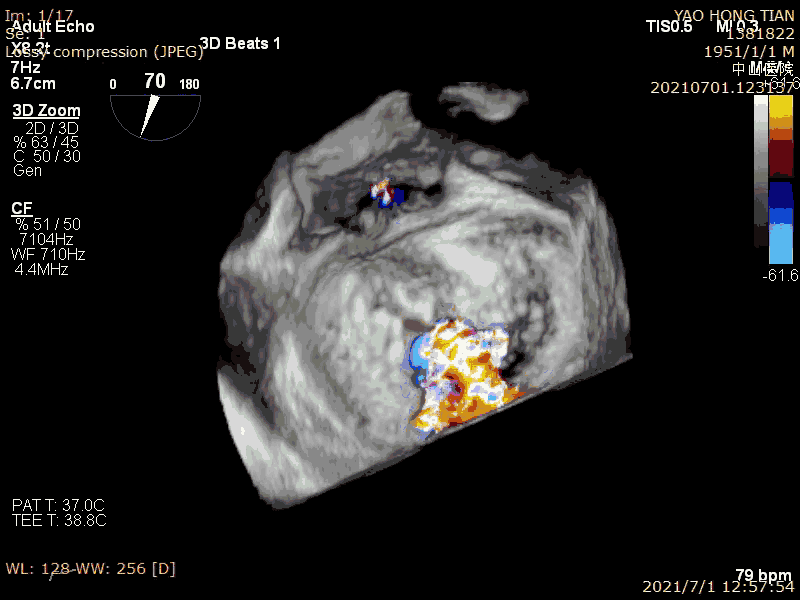

Patient: Male, 70 years old. Preoperative ultrasound diagnosis: Left ventricular ejection fraction (LVEF) 58%, left ventricular end-diastolic diameter (LVDD) 52mm, left atrial diameter (LAD) 57mm, pulmonary artery systolic pressure (PASP) 63mmHg. Severe mitral regurgitation caused by mitral valve leaflet malalignment, vena contracta (VC) 6*13mm, regurgitant area 19.8cm² (Figures 1-2).

Preoperative massive regurgitation (VC 6*13mm)

Massive regurgitation at A2P2 caused by leaflet malalignment